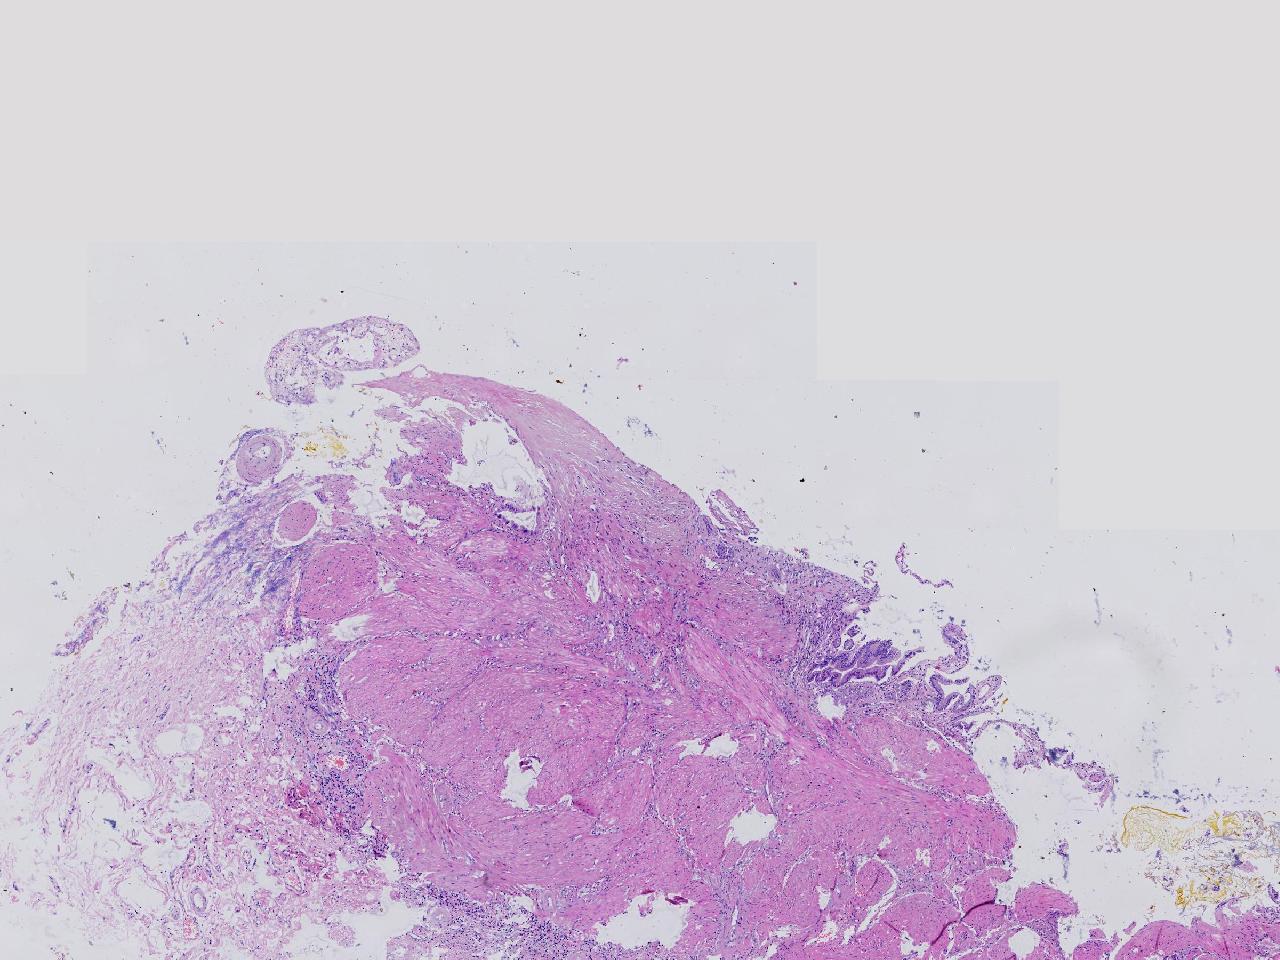

这些腺体有问题吗?

性别

女

年龄

38岁

临床诊断

胆囊结石伴慢性胆囊炎

一般病史

右上腹疼痛不适7年余,外科行胆囊切除。

标本名称

胆囊

大体所见

灰粉色胆囊一条,部分粘膜粗糙,腔内见泥沙样结石。

细胞有异型,标记看看

有异型,最好再补取几块。

这个蜡块重新制片,又多处取材制片,支持炎性反应性改变。 不支持肿瘤性。